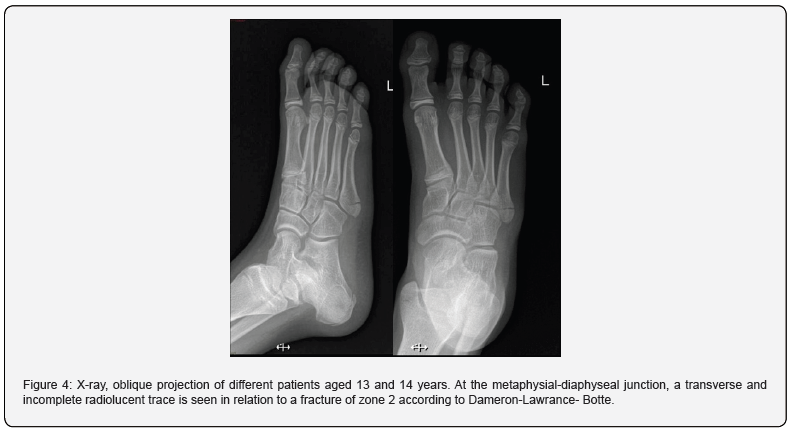

Subsequently, the fracture of the metadiaphyseal junction or zone 2, located 1.5 - 3 cm distal to the proximal end of the styloid process (Figure 4). Involves the 4th and 5th intermetatarsal joint, without participation of the metatarsocuboid joint. This fracture is favored by an adduction of the forefoot and ankle in plantar flexion [8]. And finally in terms of fractures, we find the zone 3 fracture or diaphyseal stress fracture, the least common in the pediatric population; These are located 1.5 cm proximal to the diaphysis, distal to the 4th-5th intermetatarsal joint. Its mechanism is given by repetitive overexertion. The radiographic findings consisted of an incomplete transverse fracture line without intermetatarsal joint involvement associated with a periosteal reaction. Their management is conservative, and they have an excellent prognosis.